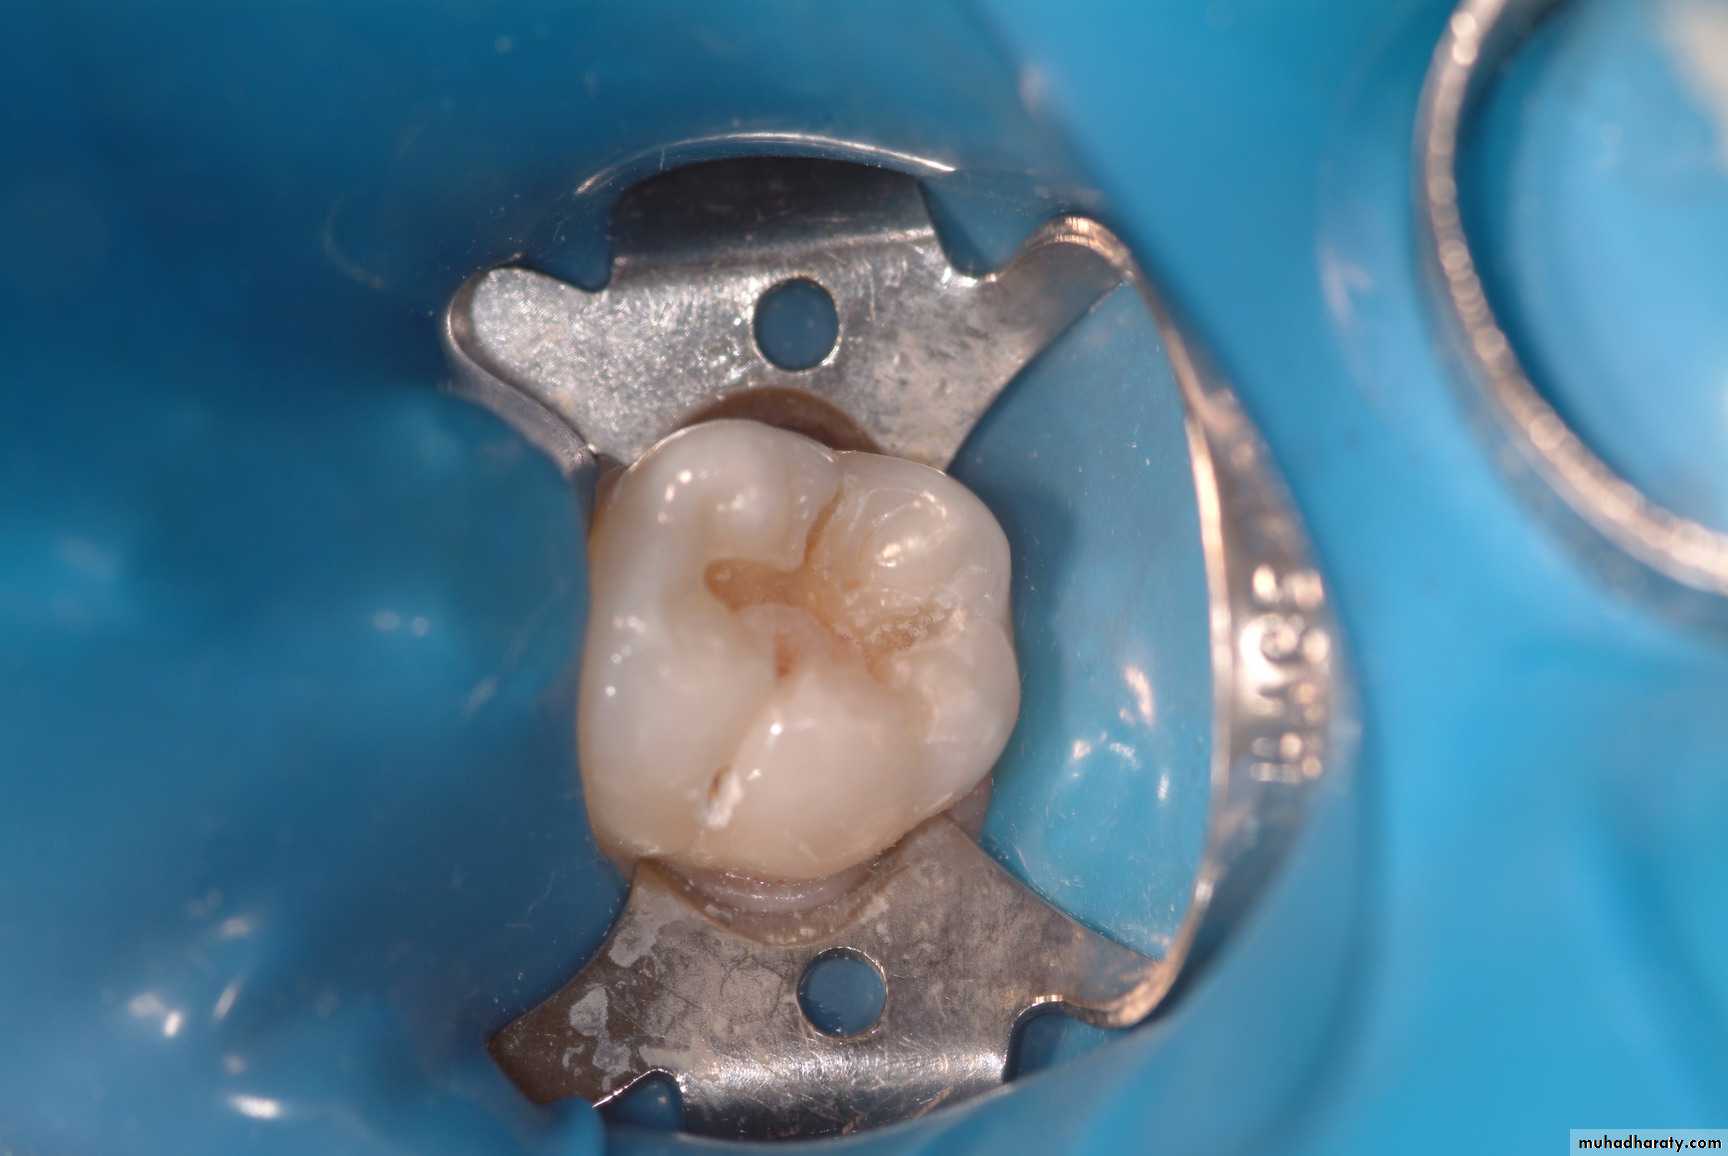

Diagnosis Of Dental Caries

Earliest caries detection, traditionally by use of mirror and light, as well as bitewing radiographs, can now be aided by new innovations in dental magnification and imaging, laser fluorescence and quantitative light-induced fluorescence.

Laser in Conservative Dentistry